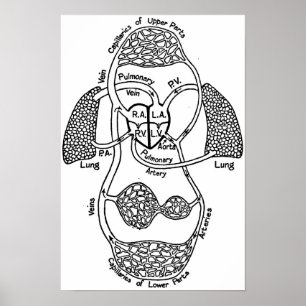

Cardiovascular Medical Diagram Poster

PriceCA$46.80